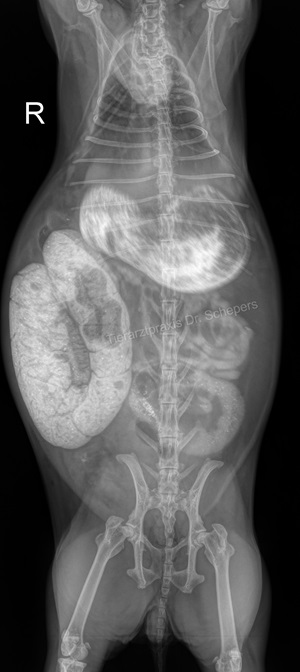

Röntgendiagnostik

Die sichere Diagnose wird durch ein Röntgenaufnahmen gestellt; hierdurch kann die Konsistenz des Mageninhalts (fest, flüssig, aufgegast) auch von weniger geübten Tierärzten sicher und objektiv beurteilt werden. Zudem besteht eine objektive Vergleichsmöglichkeit für spätere Verlaufskontrollen.

Weiterhin kann objektiv beurteilt werden, wie groß der Magen tatsächlich ist, wie lange der Zustand bereits besteht (beim mechanischen Ileus v. a. anhand der Konsistenz des Mageninhaltes: anfangs homogen, anschließend "spiegeleiartig" durch beginnende Gasbildung) sowie inwieweit eine Magentympanie (= Aufgasung) beteiligt ist. Ein gewöhnlicher Kaninchenmagen ist rund, mit homogenem, strukturiertem Inhalt gefüllt und ragt maximal zu einem Drittel über den Rippenbogen hinaus.

Auch kann die Füllung des Magen-Darm-Trakts bereits einen deutlichen Hinweis auf einen Darmverschluss liefern: Bei dem typischen, im vorderen Dünndarmbereich lokalisierten Verschluss ist die Darmschlinge unmittelbar hinter dem Magenausgang leer und luftgefüllt, der dahinter befindliche Darm hingegen noch futtergefüllt.

Sitzt der Verschluss in einem anderen Darmabschnitt, kann der Darm zu größeren Anteilen mit Luft gefüllt sein oder gefüllte, stark dilatierte (= überdehnte) Areale aufweisen. In letzterem Fall kann der Magen (noch) eine normale Größe besitzen, da sich der Futterbrei zunächst im Dünndarm und erst später bis in den Magen zurückstaut.